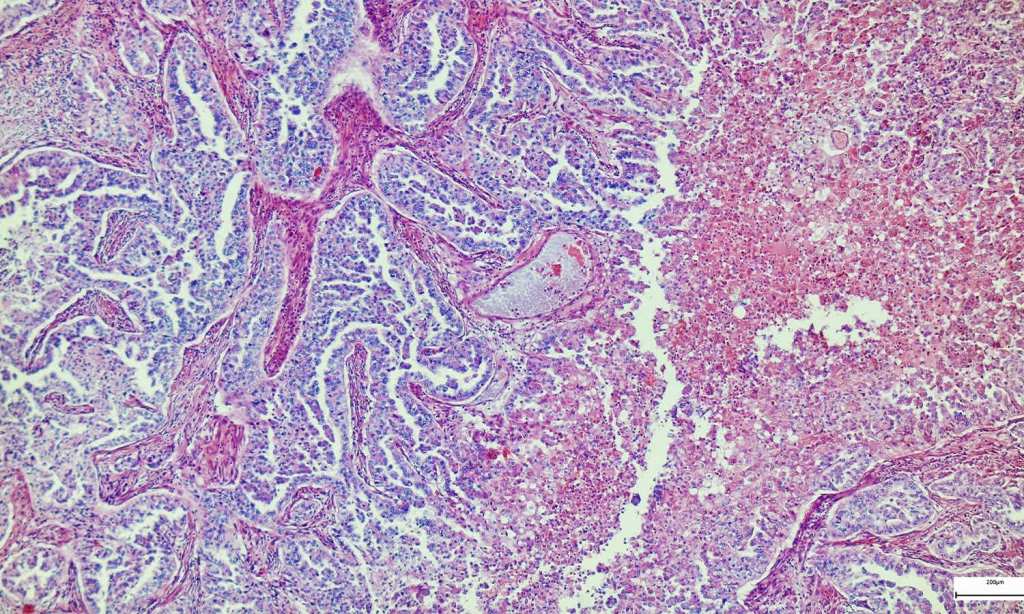

Hepatitis means inflammation of the liver, which can lead to liver failure and death. Symptoms of hepatitis include fever, fatigue, loss of appetite, nausea, abdominal pain, joint pain, and jaundice.

Hepatitis can be caused by a number of different things, including, commonly, viruses. Hepatitis viruses are named A through E and these are the ones you’d probably think of as the main cause of the illness. Parasites and bacterial infections are also common causes of hepatitis.